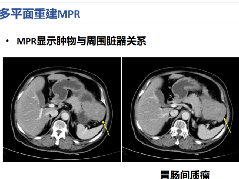

CT和MRI 检查各有其不同的特点:对于肿瘤包膜的显示MRI优于CT;对于钙化征象的显示,CT优于MRI;对于肿瘤的出血,CT和 MRI均能准确显示。CT由于可以清晰显示病灶的部位、钙化、出血及坏死,可做为HB的首选检查方法,而MRI不用对比剂可显示血管,有利于显示病灶与血管关系,且显示肿瘤范围准确,无辐射损伤,尤适用于术前检查。二者相结合,能更全面提供临床诊疗信息,有利于对手术术式的选择。

▲病例2:肝母细胞瘤。图1:CT平扫肝左右叶肿块,呈低密度,内部密度不均。图2肝内可见钙化灶。图3增强扫描肝内病灶不均匀明显强化,片状或结节状强化,见假包膜结构,图4可见肝内转移灶。